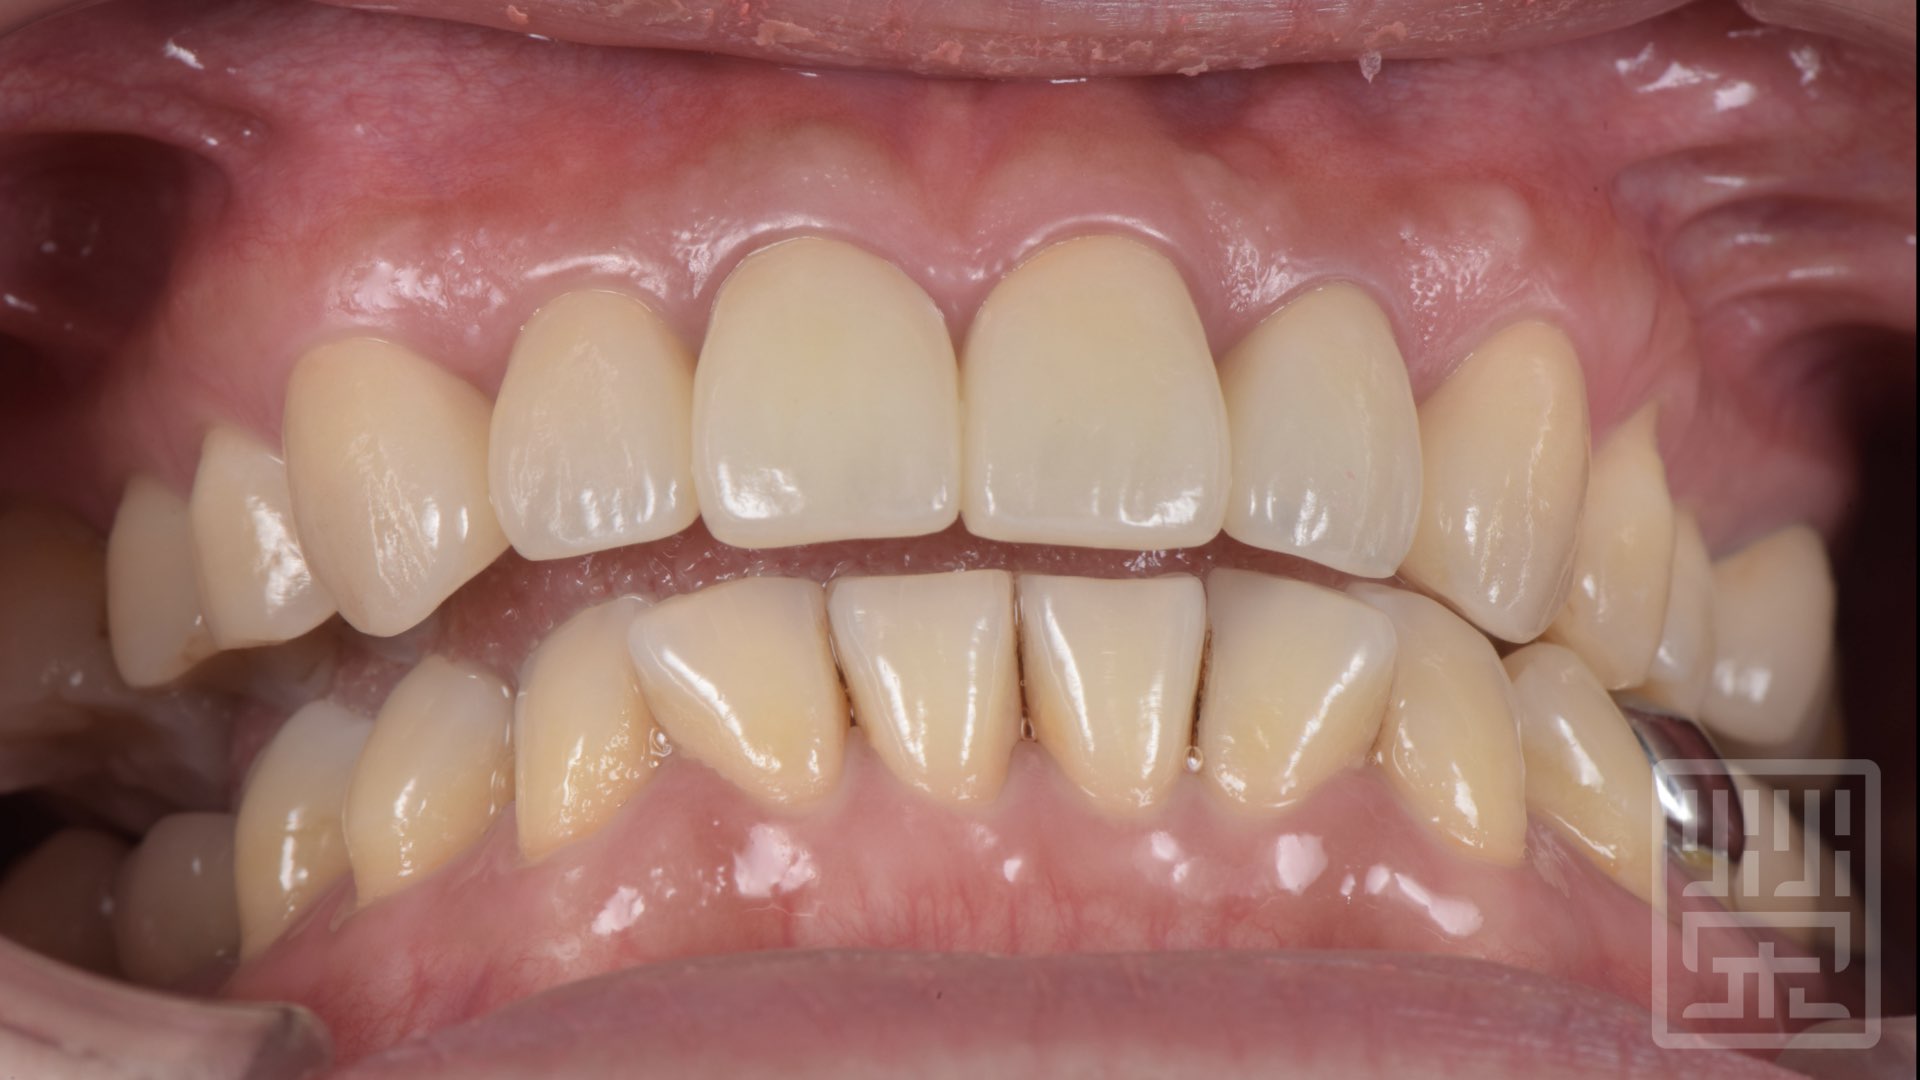

植牙全瓷冠修復

保護性咬合